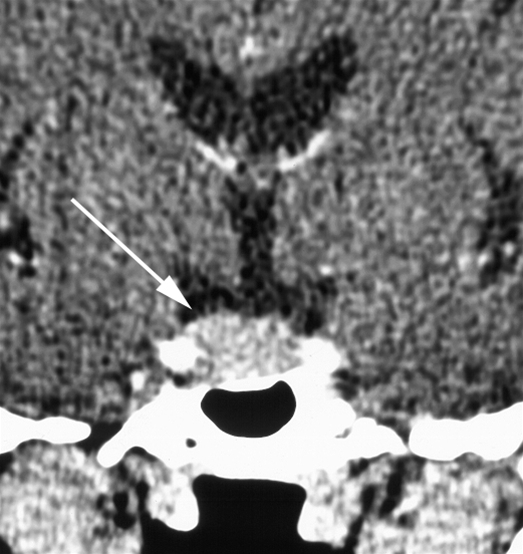

Coronalt snit gennem hypofysen efter intravenøs kontrastinjektion. Hypofysen (pil) er generelt forstørret, med konvekst buende konturer.